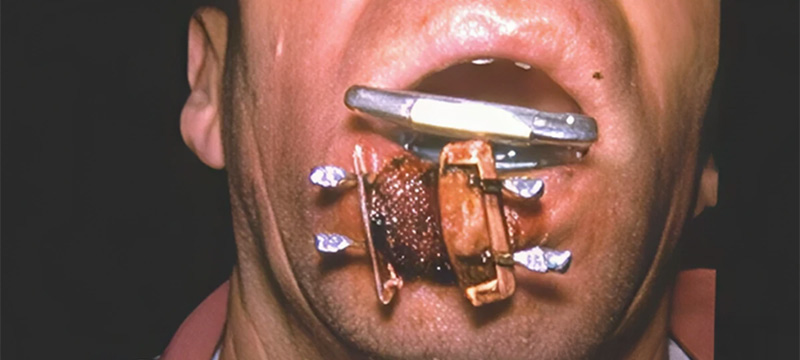

Fig. 02.

Fig. 02.

L’endocuriethérapie est une irradiation in situ : des aiguilles de césium 132 ou d’irridium (IR 192) radioactifs sont mis en place dans la tumeur. Ces aiguilles sont laissées en place 8 à 10 jours, délivrant environ 70 Grays. Les mucites peuvent être très invalidantes.